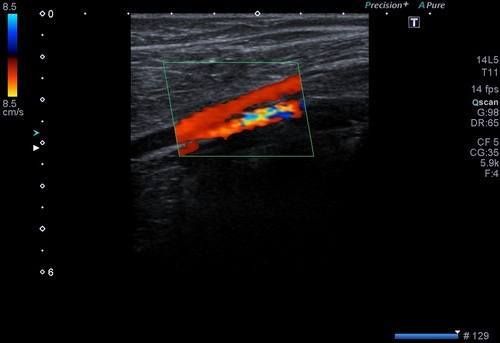

Bu incelemede atardamarlardaki tıkanıklıklar, darlıklar, plaklar değerlendirilir. Damarlardan geçen kanın akım hızları ve debileri ölçülür.

Hipertansiyon, yoğun sigara içiciliği, kolesterol yükseklikleri ve bazı kalp damar hastalıklarında kol ve bacak atardamarlarında damar sertliği bulguları, plaklar veya tıkanıklıklar görülebilir. Bu durumda renkli doppler ultrason ile olası darlıkların dereceleri, plak boyutları, akım hızlarındaki artışlar değerlendirilerek nasıl bir tedavi yapılacağı kararı verilir.